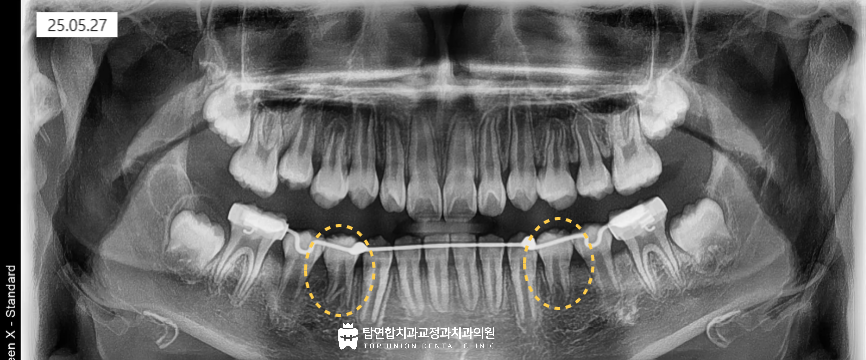

치료 과정에서는 앞으로 맹출될 제2소구치와

현재 자리를 차지하고 있는 제2유구치의

좌우 폭경 차이를 이용해 공간을 확보하며

비뚤어짐 없이 제1소구치가 자연스럽게

맹출할 수 있도록 조정하였습니다.

치료 중에는 치근 흡수나 교합 이상이 발생하지 않도록

정기적인 엑스레이 검사로

치아 이동 방향을 면밀히 관찰하였습니다.

이러한 세심한 조정을 통해 이어서 맹출하는

두 번째 작은 어금니와 함께

제1소구치는 정상 위치로 맹출 되었고

아래쪽의 영구치열이 고르게 완성되었습니다.